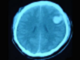

98.患者,女,52岁。有高血压病史,半小时前突感头晕,剧烈头痛,摔倒在自家楼下,CT检查如图所示,最可能的诊断为()